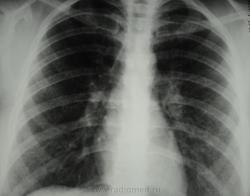

По рентгенограммам, создается впечатление превалирования "изменений", преимущественно, в средних и нижних отделах легочных полей.

Изменения диффузны. По rg более выраженны в нижних отделах, за счет марсива тканей. Ждем анализ мокроты и промывных вод.